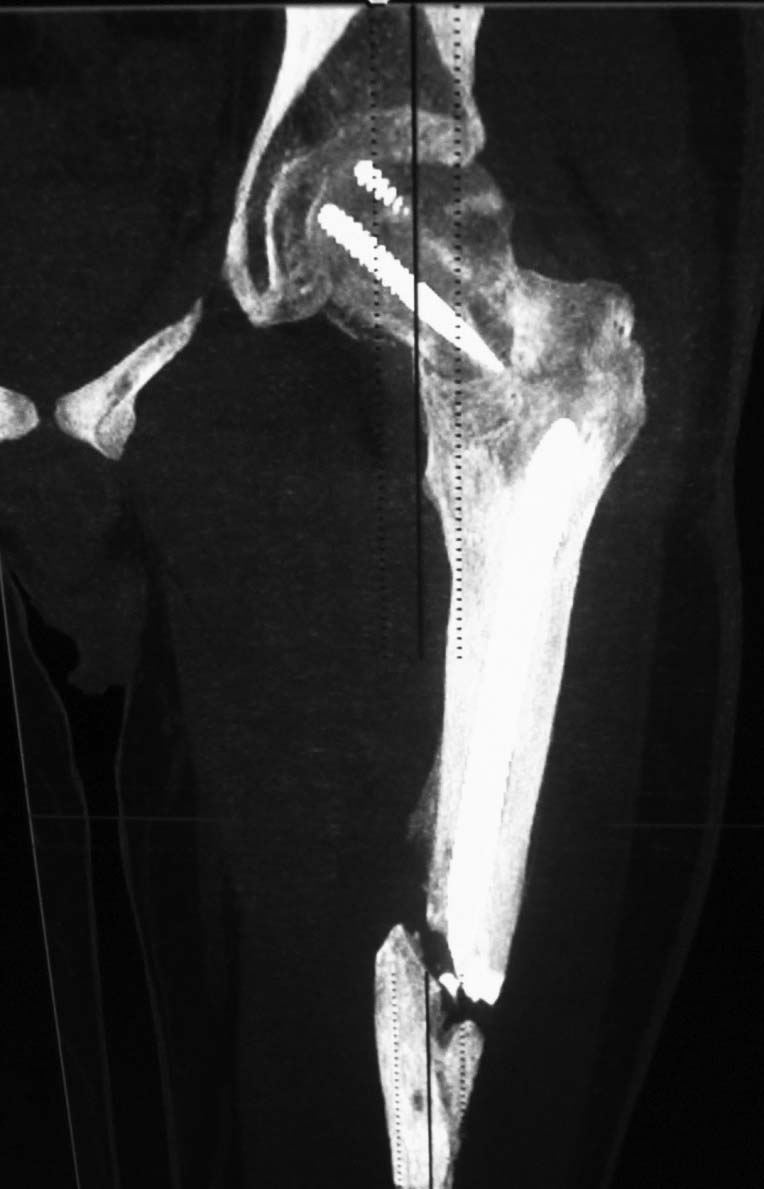

У Синтеза специально для таких двойных переломов есть латеральный бедренный гвоздь, позволяющий увеличить расстояние между гвоздем и линией перелома шейки за счет смещения кнаружи точки введения гвоздя. Во вложении - трехлетней давности пример: остеосинтез выполнен через полтора месяца после травмы, вполне удалась закрытая репозиция проксимального перелома. Единственный непонятный для меня момент такой операции - невозможность динамизации диафизарного перелома без удаления фиксаторов из головки. В представленном случае шейка срослась быстро, а вот диафиз - только после удаления верхних винтов и установки винта в динамическое отверстие в подвертельной области.